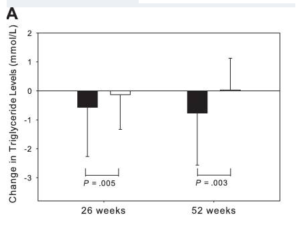

Araştırmalar, tesamorelin’in lipodistrofiyi azaltmanın yanı sıra, trigliseridleri, toplam kolesterolü ve non-HDL-C seviyelerini de düşürdüğünü göstermektedir. Tesamorelin ile viseral yağ dokusunda %15 azalma, trigliserid seviyelerinde 50 mg düşüş ile ilişkilidir [3], [4].